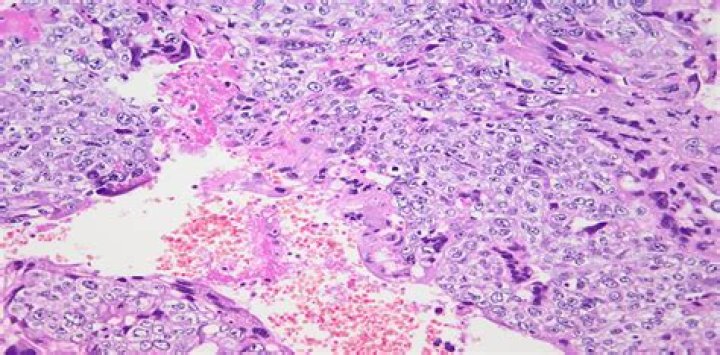

What happens in choriocarcinoma?

Choriocarcinoma is a fast-growing cancer that occurs in a woman’s uterus (womb). The abnormal cells start in the tissue that would normally become the placenta. This is the organ that develops during pregnancy to feed the fetus.

Unlike a hydatidiform mole, a choriocarcinoma is a malignant and more aggressive form of GTD that spreads into the muscle wall of the uterus. A choriocarcinoma can also spread more widely to other parts of the body such as the lungs, liver, and/or brain.

Invasive mole is unlike choriocarcinoma, the latter is without the presence of chorionic villi. It is important to distinguish between invasive mole and choriocarcinoma, as the former has a more favorable outcome.